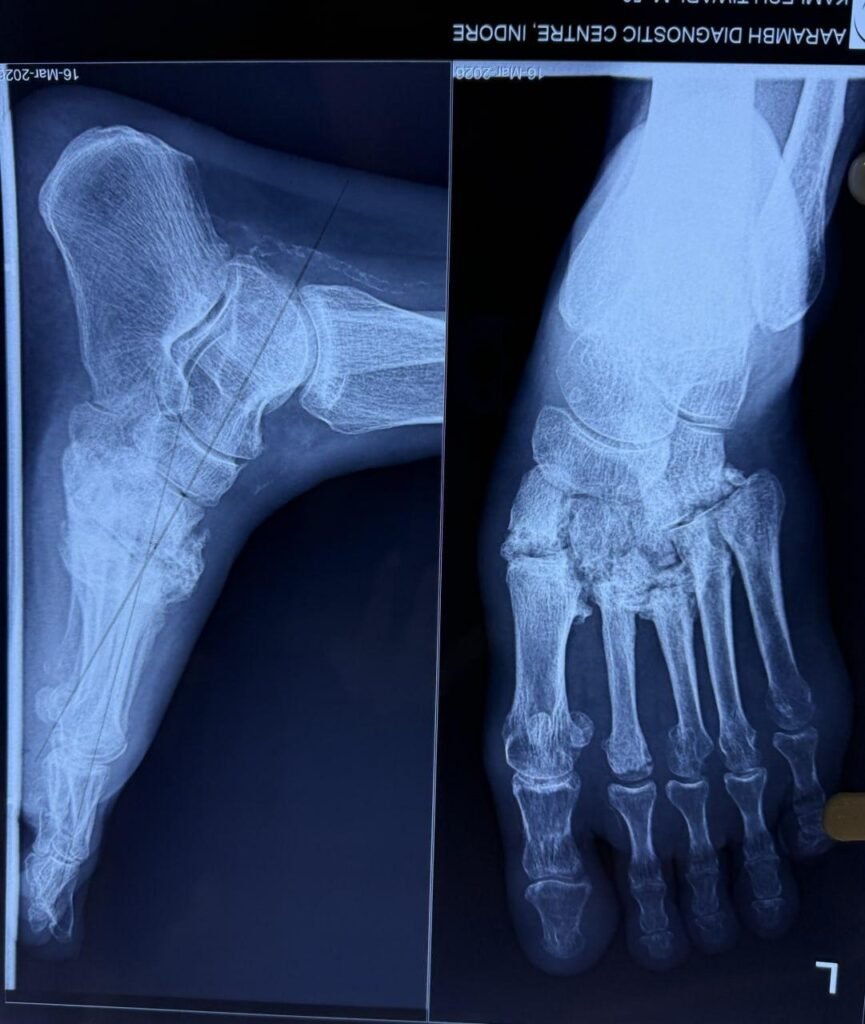

Minimal invasive calcaneum fracture surgery                                </p>

Minimal invasive calcaneum fracture surgery

Minimal invasive calcaneum surgery repairs heel fractures with small cuts, less pain, and quicker recovery.